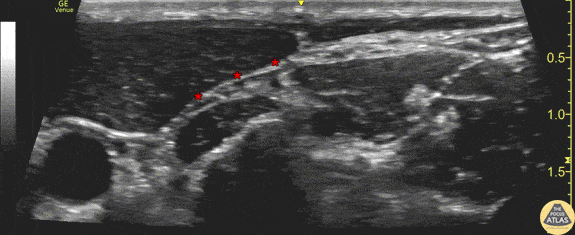

Demonstration of the anatomy of the superficial cervical plexus. The posterior border of the sternocleidomastoid muscle is seen at the center left of screen, and the target fascial plane for a superficial cervical plexus nerve block is highlighted (*). The pulsating carotid artery is seen at the anterior aspect of the image. Drs. Sam Paskin-Flerlage, PGY4 and Michael Heffler, PGY3 Denver Health Residency in Emergency Medicine